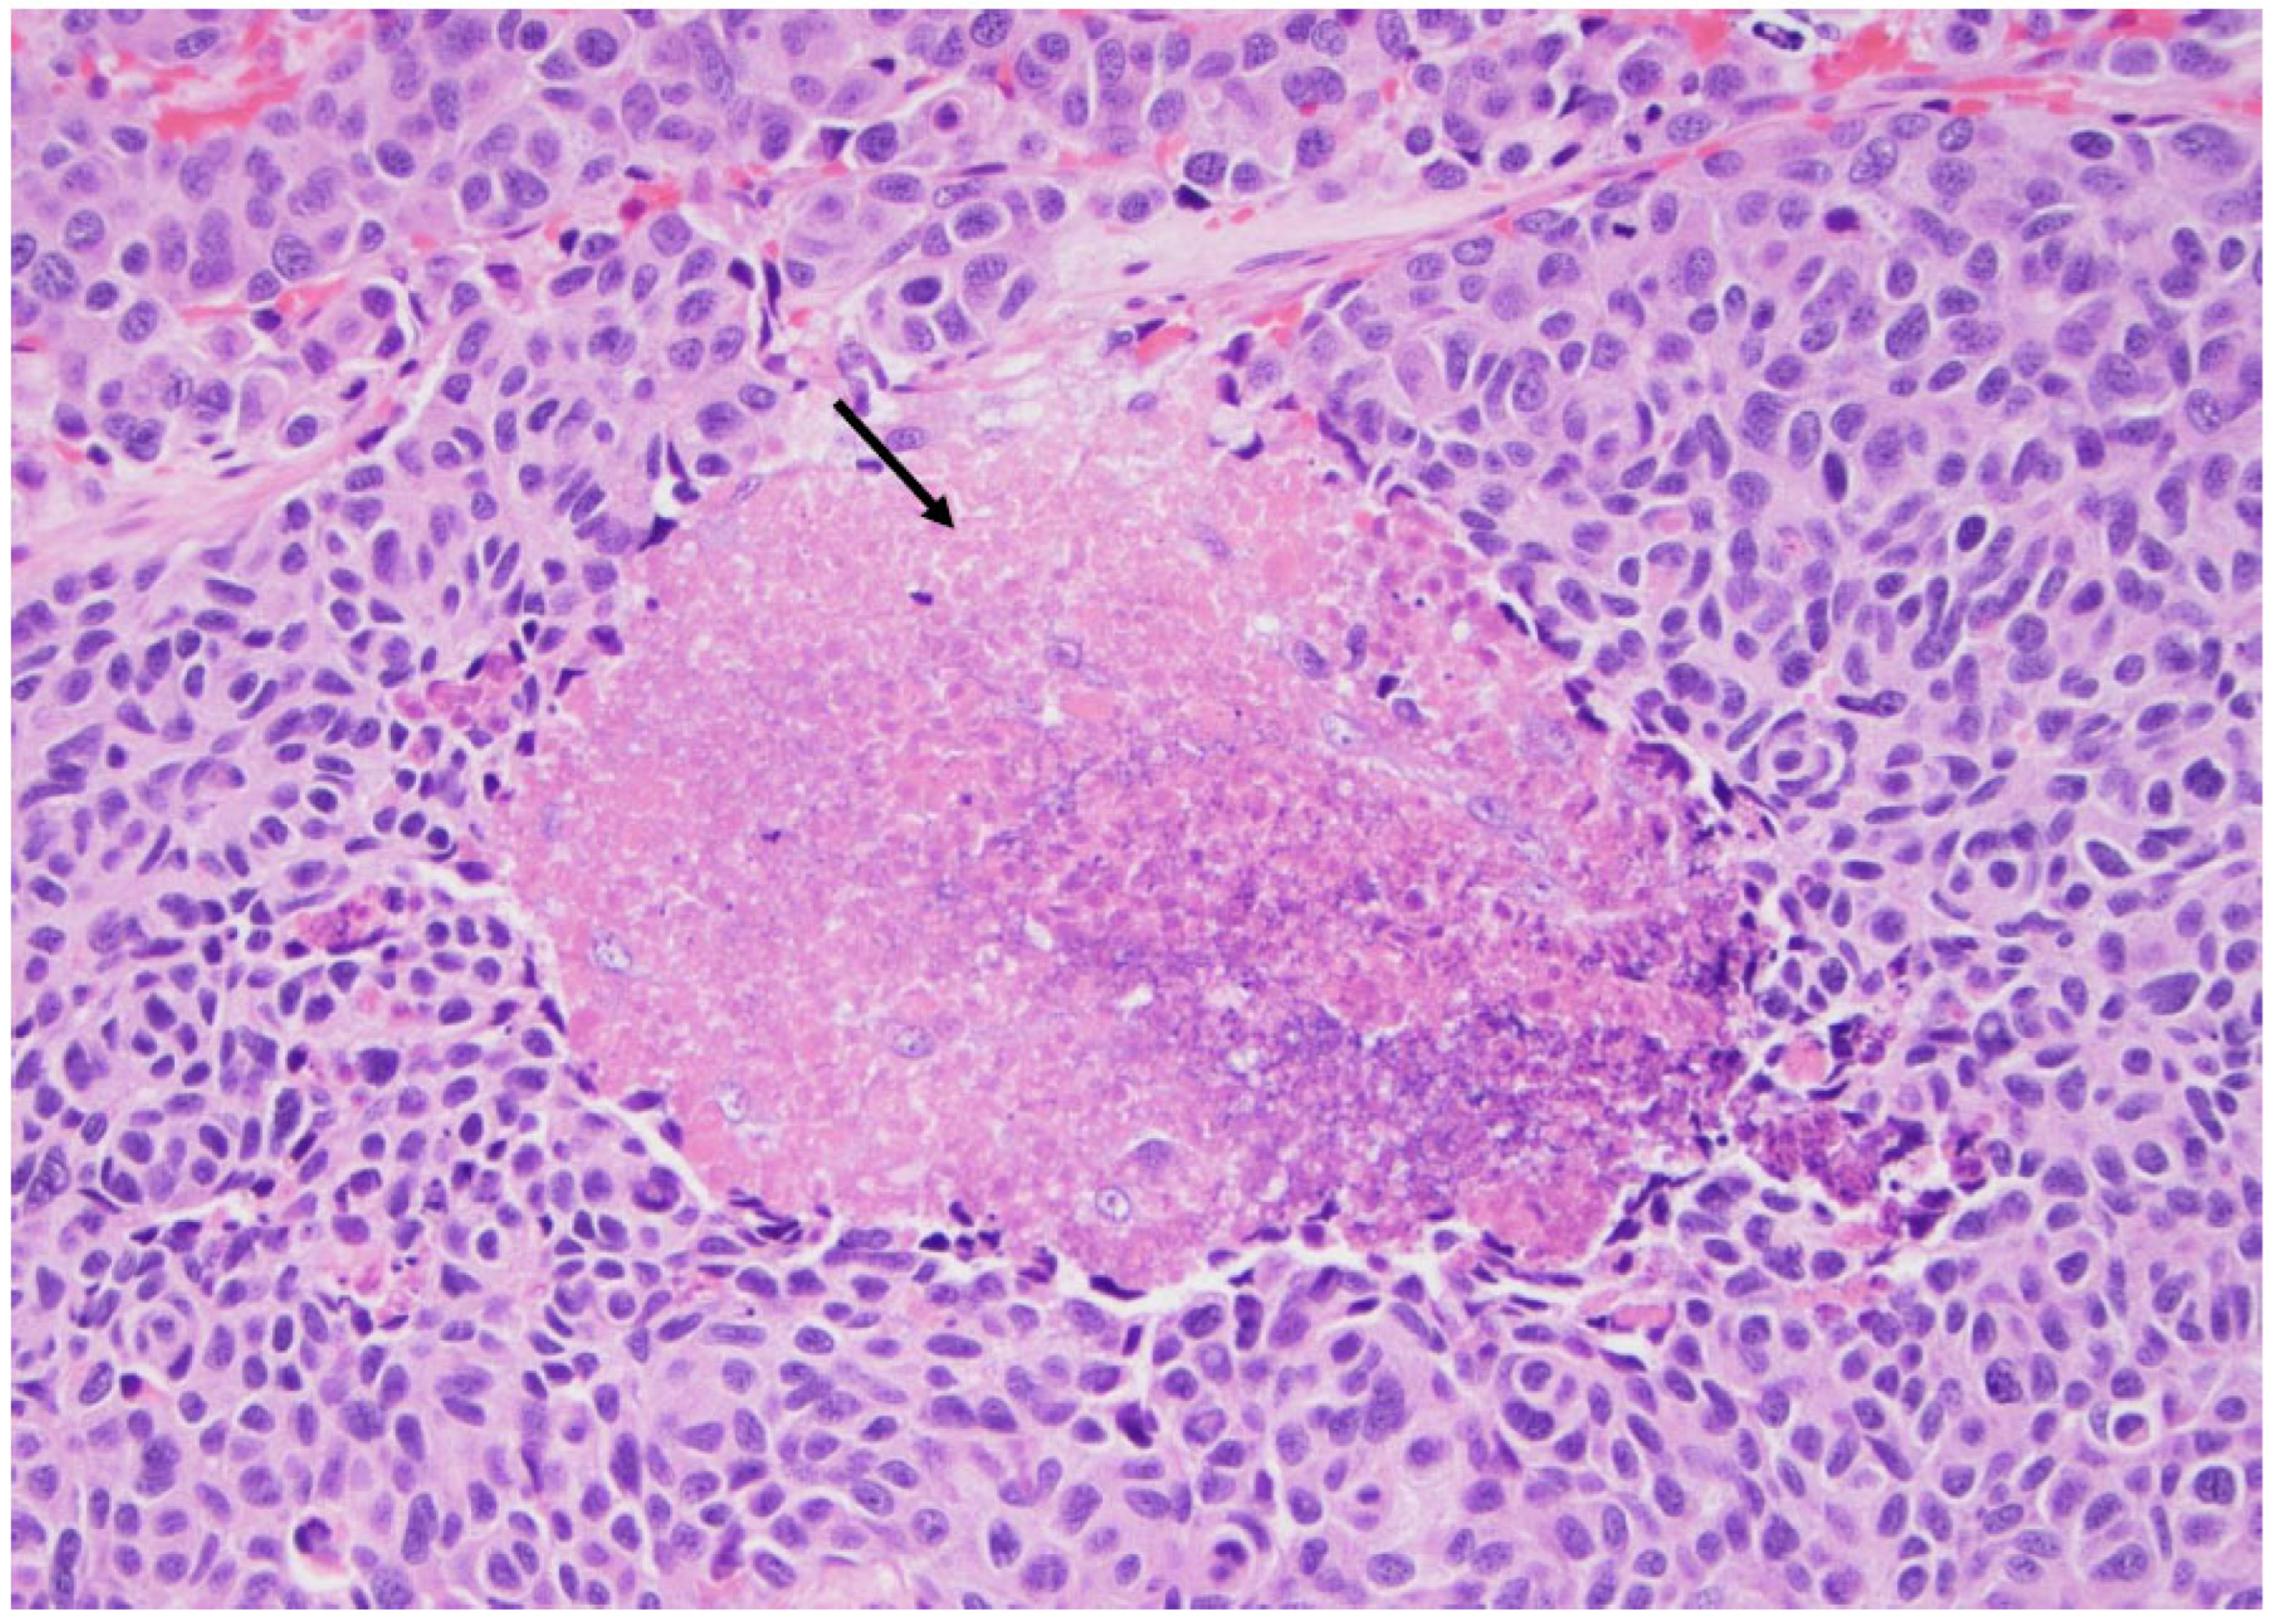

Figure 6. High-grade carcinoma; the same tumor with trabecular and solid patterns with an area of extensive necrosis (arrow) (×200, H&E stain).